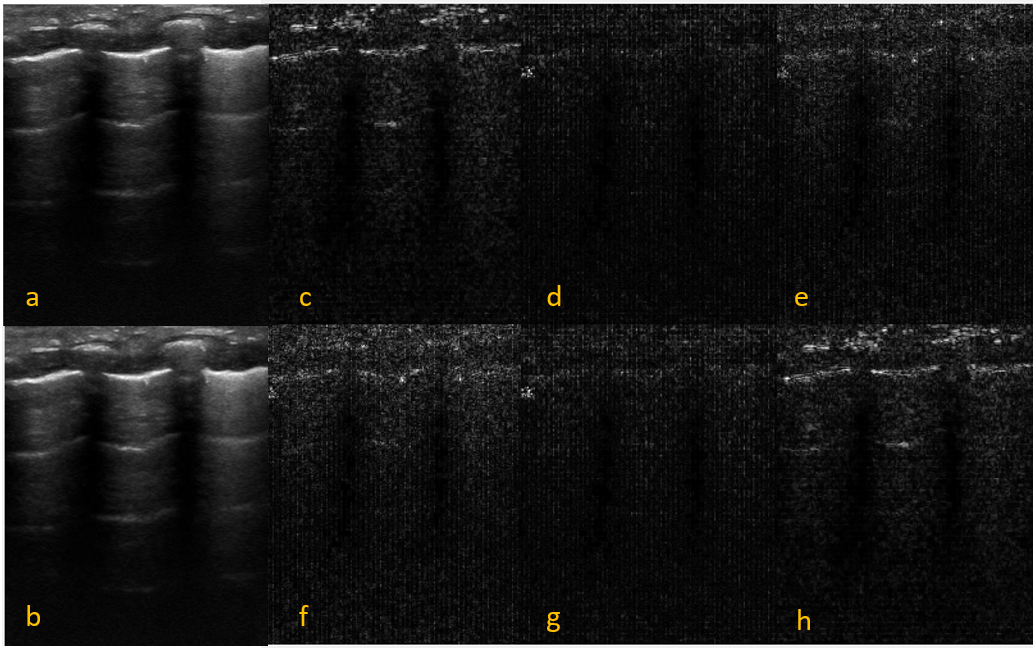

Refer to caption

Figure 2: a: A sample normal Pleura from a subject with Normal Lung, b: A sample thick Pleura (>> 2mm) from a subject with CON, c: A sample thick and irregular Pleura from a subject with CLD, d: Sample A-Lines from a subject with PTX, e: Sample separate B-Lines from a subject with TTN, f: Sample coalescent B-lines from a subject with RDS, g: Sample CON illustration from a subject with Consolidation, and h: Sample Double Lung Point from a subject with TTN